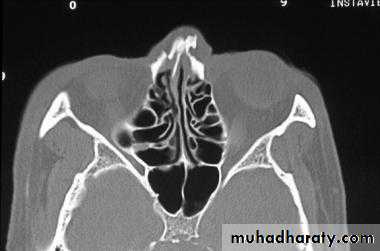

Radiographic Evaluation

1- Lateral views of nasal bone, 15 or 30 degree occipitomental projections can be taken.2- CT scan for higher level of nose fractures.